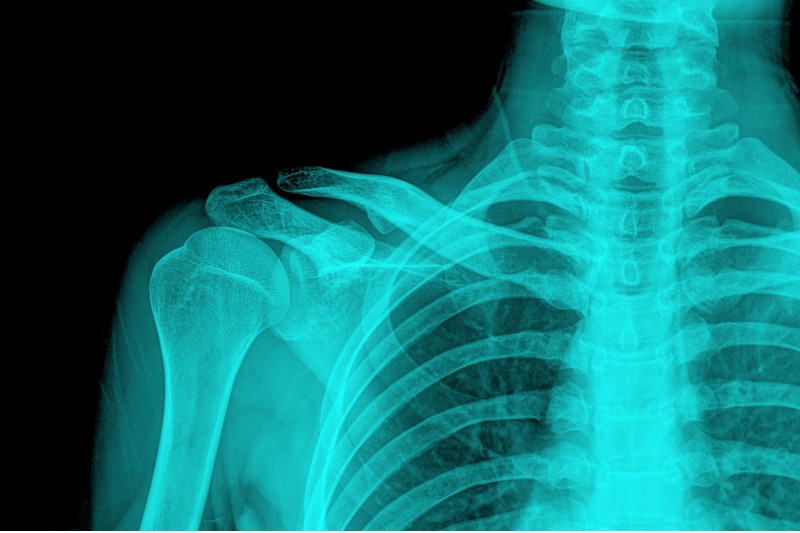

Vállműtétek - vállprotézis

Vállsérülések vagy vállfájdalmak esetén célunk, hogy modern sebészeti eljárásokkal segítsük a gyors és biztonságos gyógyulást.

A váll műtétek alábbi fajtáit biztosítjuk pácienseinknek: